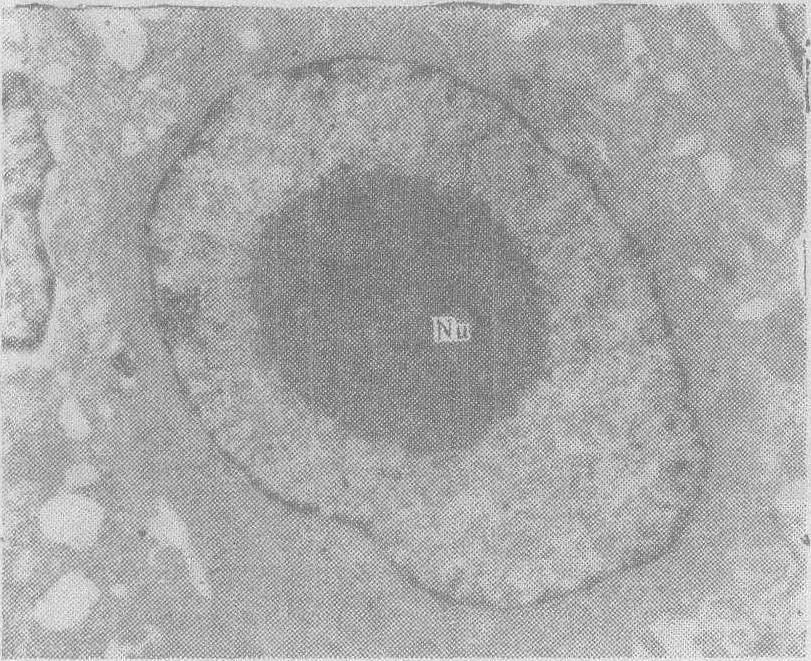

图5 癌细胞核及核仁(Nu)明显增大,核仁致密,细胞质少×18000

(3)蛋白质合成及细胞分裂功能旺盛: 蛋白质合成虽是一种功能状态,但在形态上也有各种表现。首先是核的体积大,核内常染色质丰富;核仁大,且数目增多;核周间隙扩大,核膜孔明显可见。核虽然一般都增大(即核浆比例大)(图5),但有少数恶性肿瘤如有的甲状腺癌,胞核常无明显增大。此外,如印戒细胞癌,细胞质被大量粘液泡所占据,核被挤向一侧,显得反而变小。有的恶性肿瘤细胞核中常染色质十分明显,异染色质在近核膜处较多,在光学显微镜下形成核膜深染,核显得空而明亮,即所谓空泡状核。在电镜下观察,此种核的明亮区域,仍可见到稀疏的细颗粒状结构,即常染色质区。另一类核的异染色质较明显,聚集成小块,散在分布于核中。在光学显微镜下,亦可见核中有深染的染色小块,与周围明亮区域成清楚的对比。核仁常显著增大,一般为圆形,也可为椭圆形,或为不规则形,位于核中心,或近核膜处,或横跨核内。核仁内部的结构呈海绵状,即在电子密度大的区域间,有密度小的区域;或呈盘绳状,即电子密度大的区域与电子密度小的区域分层相间出现;或呈实体状,即成为完全致密的区域。有人曾用放射自显影及分层离心法观察白血病细胞在细胞动力学周期中,核的超微结构有变化,发现异染色质与常染色质的比例,核仁的大小、形状及位置与细胞动力学周期有一定关系。核及核仁的各种超微结构变化,说明癌细胞处于细胞动力学周期的不同阶段。恶性肿瘤中核分裂象也比较多见,其超微结构的变化,除分极有时不对称外,与正常细胞的核分裂类似。细胞质内游离核蛋白体比较丰富,主要是合成瘤细胞本身增殖所需的蛋白。